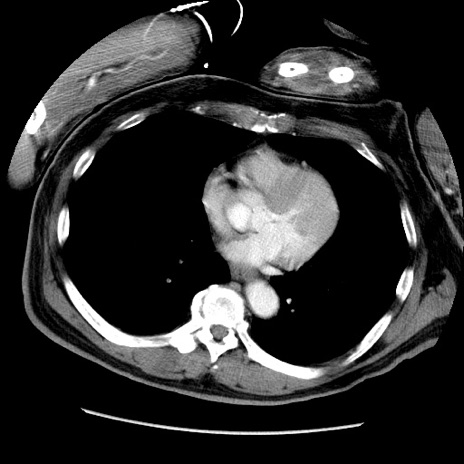

症例22(横断像)

【症例】50歳代男性

【主訴】腹痛

【現病歴】AVMからの被殻出血のため回復期リハ病棟入院中。 本日午後3時頃急に下腹部痛が出現した。

【既往歴】AVM、被殻出血、虫垂炎、高血圧

【身体所見】意識晴明、左半身不全麻痺、会話の理解は良好、36.5°C、腹部:膨隆、全体に板状硬、下腹部正中に圧痛点あり、反跳痛-、筋性防御不明、右下腹部にope scar

【データ】WBC 9400、CRP 0.06